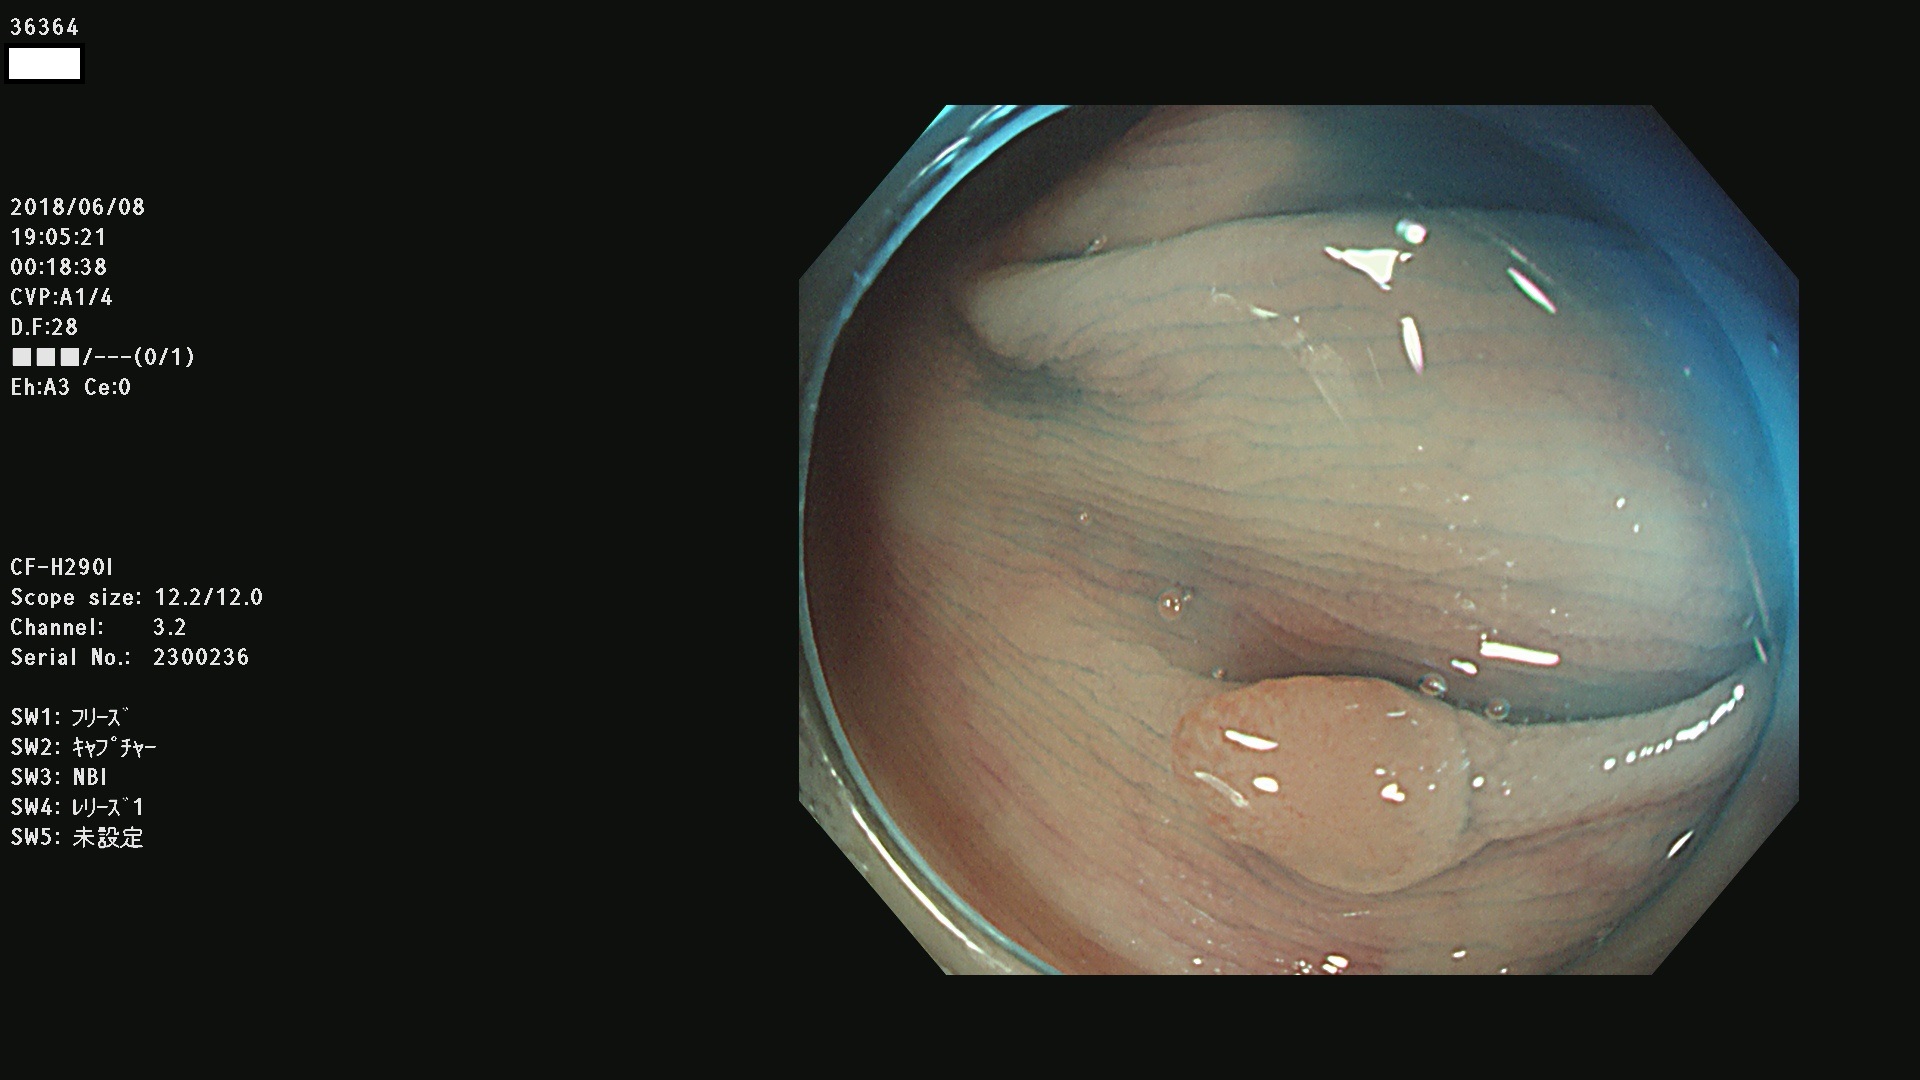

腺腫発見率 68 % (カルテ番号 36300〜36399の100名の方の検査結果で集計)大腸癌検診最新情報

以下のカルテ番号の方に腺腫(Adenoma,Group3〜5)が見つかりました(集計法)

36300 36302 36305 36306 36307 36308 36310 36311 36312 36313 36314 36315 36316 36318 36321 36322 36324 36325 36326 36327 36330 36332 36333 36334 36335(SSAPのみ) 36337 36338 36339(SSAPのみ) 36340 36341 36342(SSAPのみ) 36343 36344 36346 36348 36349 36351 36353 36354 36355(SSAPのみ) 36356 36357 36358 36359 36364 36365 36366 36367 36370 36374 36376 36379 36381 36382 36383 36384 36385 36387 36388 36389 36390 36392 36393 36395 36396 36398 36399

発見困難で危険性の高い平坦型病変(上記100名より抽出) ![]()